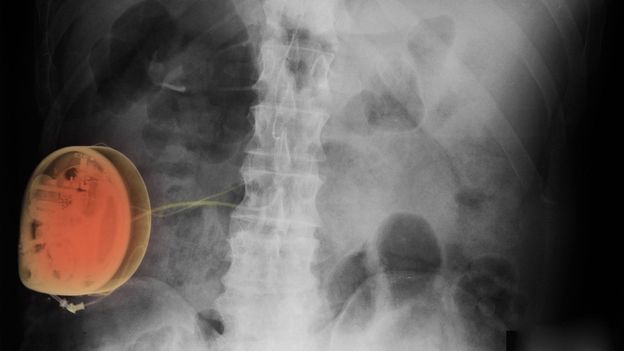

Scott Camazine/Science Photo Library“We were the first centre in the world to pioneer spinal cord stimulation,” says Al-Kaisy proudly. “We try to send small bolts of electricity to the spinal cord by inserting a wire in the epidural area. It’s only one or two volts, so the patient feels just a tingling sensation over where the pain is, instead of feeling the actual pain. The patient feels nothing except his pain going down. It’s not invasive – we usually send patients home the same day.”

When Carter, the chap with the agonised groin, had failed to respond to any other treatments, Al-Kaisy tried his box of tricks. “We gave him something called a dorsal root ganglion stimulation,” says Al-Kaisy. “It makes the spine hyperexcited, and sends impulses to the spinal cord and the brain. Over ten days the intensity of pain went down by 70 per cent – by the patient’s own assessment.

“He wrote me a very nice email saying I had changed his life, that the pain had just stopped completely, and that he was coming back to normality. He said his job was saved, as was his marriage, and he wanted to go back to playing sport. This is a remarkable outcome. You cannot get it from any other therapies.”